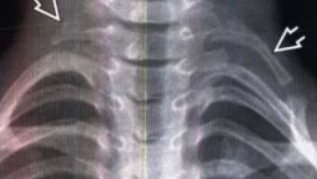

Хирургическое лечение синдрома грудного выхода

Синдром грудного выхода (СГВ) представляет собой симптомокомплекс, возникший в результате механического сдавления извне первичных нервных стволов плечевого сплетения и подключичных сосудов при их выходе из верхней грудной апертуры в сторону шеи и верхних конечностей [1-5]. Анатомо-морфологическими исследованиями было показано, что область грудного выхода имеет сложную анатомическую структуру, состоящую из трёх последовательных узких пространств - выходов: верхнее пространство при выходе из грудной клетки, рёберно-лестничное пространство и рёберно-ключичный промежуток [6, 7]...